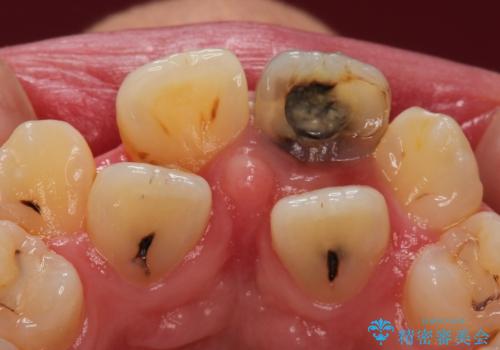

- 前歯が黒くなってきたことを主訴に来院された患者様です。

精査したところ、う蝕により歯の内側から黒くなっていました。

根管治療後、セラミッククラウンによる補綴を行いました。

※う蝕が大きく健全歯質が非常に薄いため、長期的予後に関しては不明であることをご理解頂いた上で治療を行いました。